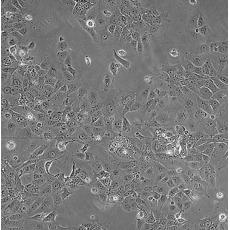

產(chǎn)品名稱 HCC827

商品貨號 MZ-0072

中文名稱 人非小細胞肺癌細胞

細胞數(shù)量 1*10^6

組織來源 肺腺癌;女性

細胞種屬 Homo sapiens, human

細胞污染 HIV-1、 HBV、HCV、支原體、細菌、酵母和真菌檢測陰性。

生長特性 adherent

培養(yǎng)基 RPMI-1640+10% FBS+1% P/S

形態(tài)特征 epithelial

傳代方法 1:3-1:6

培養(yǎng)條件 Atmosphere: Air, 95%; CO2, 5%。Temperature: 37℃

細胞描述 This lung adenocarcinoma has an acquired mutation in the EGFR tyrosine kinase domain(E746-A750 deletion).